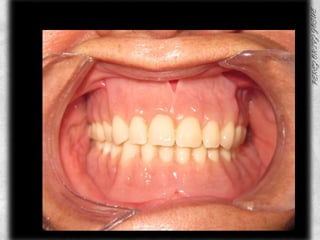

PROTESIS TERMINADA

AJUSTE OCLUSAL

COMPARATIVOS